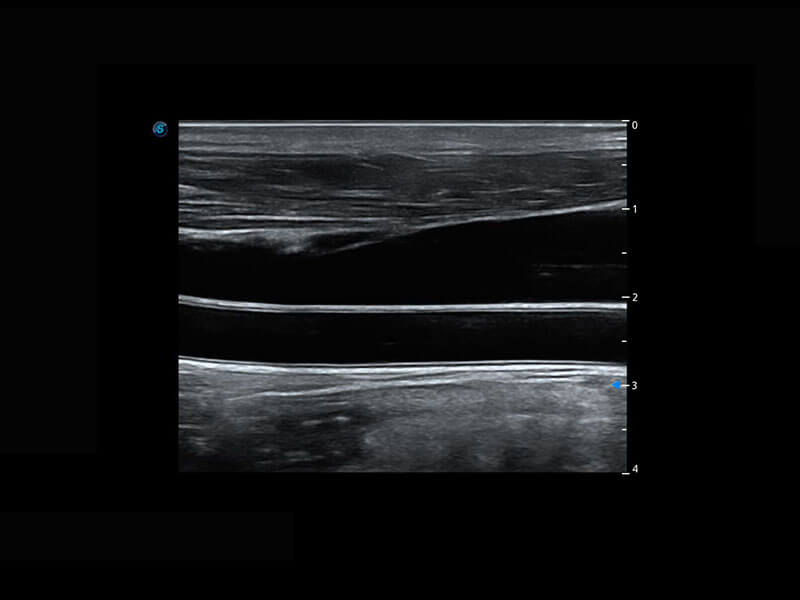

乳腺超声 / 新生儿

P60搭载宽频带线阵探头、宽景成像、弹性成像技术,为您提供乳腺应用方案。P60支持高频相控阵探头、线阵探头、腹部高频探头、腹部微凸探头等,丰富的探头群搭载敏感的彩色血流成像,适用于新生儿多种脏器检测要求,满足新生儿筛查需求。

• 乳腺导管癌

• 乳腺癌显微血流